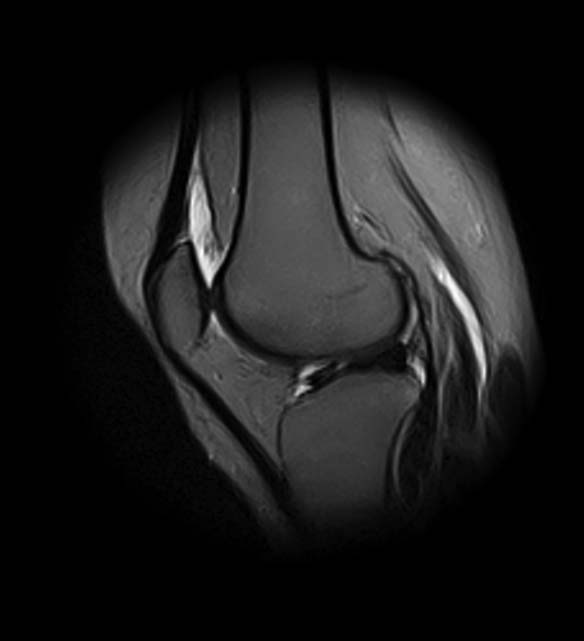

[Ortho] Показания для артроскопии

1. травма 5 лет назад - "ударилась коленом", с тех пор боли в суставе

3. стандартные рентгенограммы с небольшими изменениями - сужение

медиальной суставной щели

4. вес пациентки 80 кг, рост 165

5. сустав клинически стабилен